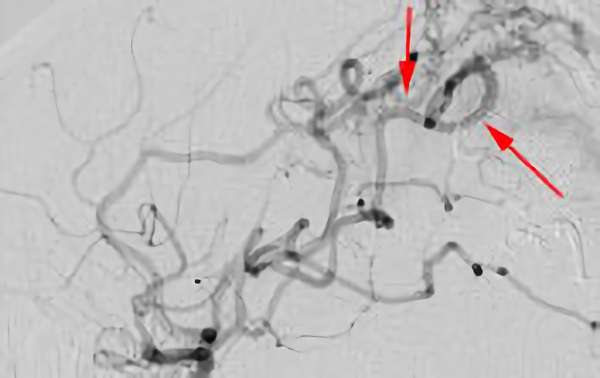

No.1576 手術前

No.1576 手術中

No.1576 手術後